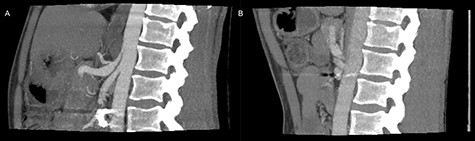

On admittance the patient had a pulse of 113 BPM, blood pressure of 125/60 mmHg and were anemic with a hemoglobin of 4.7 mmol/L. The patient underwent emergency contrast enhanced CT of both abdomen and cerebrum in venous phase without any pathological findings. Initial upper gastrointestinal endoscopy revealed a pulsating duodenal hemorrhage which could not be controlled endoscopically, and a laparotomy with duodenotomy and surgical hemostasis of a pulsating mucosal artery was performed. No classic duodenal ulceration was seen during neither gastroscopy nor duodenotomy. The patient was discharged 3 days later, but readmitted 6 days postoperatively due hematemesis and syncope. An emergency CTA showed stenosis and post-stenotic dilatation of CA and an aneurysm on a jejunal branch artery. The patient was circulatory stable and transferred to a tertiary center and underwent successful coiling of the gastroduodenal artery, gastroepiploic artery and two pancreaticoduodenal arterial branches. One month later a CTA, following a dedicated MALS protocol, visualized hook deformation of CA during expiration, significant stenosis and post-stenotic dilatation of CA (Fig. 1), all considered pathognomonic for MALS. An additional pseudoanurysm on the pancreaticodorsal artery was identified. The MALS angiographic protocol was performed using contrast-enhanced (100 ml Omnipaque 350 mg/ml, 3 ml/s) arterial scans in a maximum inspiratory phase followed by a maximum expiratory phase was performed with a 5 s delay between the respiratory phases.

Preoperative inspiratory (A) and expiratory (B) computed tomography scan, visualizing hook formation and stenosis of the celiac artery.